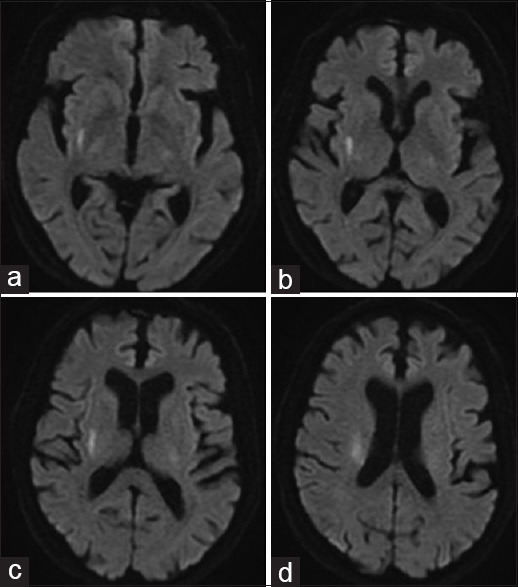

背景:对于动脉粥样硬化性或微动脉粥样硬化性急性缺血性卒中患者,替罗非班在 3 个月后实现功能独立方面优于阿司匹林。由于静脉溶栓(IVT)在治疗前脉络膜或旁侧桥脑梗死(ACI/PPI)3个月后实现功能独立方面不优于阿司匹林,我们旨在比较接受静脉溶栓加替罗非班(IVT + T)和单纯接受替罗非班治疗急性ACI/PPI的高加索患者的疗效:我们对 2020 年 12 月 1 日至 2023 年 4 月 30 日期间在我院卒中单元接受治疗的 ACI/PPI 患者(年龄≥18 岁)进行了回顾性研究,这些患者在症状出现 9 小时内或在卒中症状苏醒后接受了治疗干预。3个月时改良Rankin量表(mRS)≤1为主要终点。次要终点是第7天或出院时美国国立卫生研究院卒中量表(NIHSS)≤2和72小时内术后神经功能恶化(PPND)。无症状性颅内出血(SICH)和全身大出血(MSB)是研究的安全性指标:结果:共有24名患者加入替罗非班组,43名患者加入IVT + T组。与单用替罗非班相比,IVT + T与3个月时mRS≤1的概率更高相关(调整后的几率比[aOR],8.79;95%置信区间[CI],2.06-37.52;P = 0.003),与第7天或出院时美国国立卫生研究院卒中量表≤2相关(aOR,3.70;95% CI,1.05-12.99;P = 0.041)。两组患者在预防术后神经功能恶化方面无明显差异。IVT+T组发生了1例SICH和2例MSB,而替罗非班组没有发生SICH和MSB。IVT+T组出现一例院内死亡:我们的研究结果表明,对于急性 ACI/PPI 的高加索患者来说,IVT + T 可能是安全有效的。

Methods: A retrospective study was conducted in patients aged ≥ 18 years with ACI/PPI treated in our stroke unit between December 1, 2020, and April 30, 2023, who received therapeutic intervention within 9 hours of symptom onset or after awakening with stroke symptoms. Modified Rankin Scale (mRS) ≤ 1 at 3 months was the primary endpoint. Secondary endpoints were National Institutes of Health Stroke Scale (NIHSS) ≤ 2 at day 7 or discharge and post-procedural neurological deterioration (PPND) within 72 hours. Symptomatic intracranial hemorrhage (SICH) and major systemic bleeding (MSB) were the safety measures of the study.